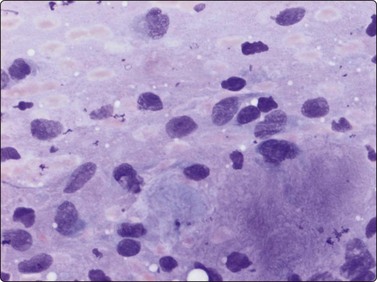

The pseudosarcomatous lesions are an important target for needling in this histogenetic group of tumors/lesions. Nodular fasciitis is among the commonest and the most frequently needled. Dahl and Åkerman reported 13 cases with cytology 1981;12 at present, our material comprises more than 70 cases, all with remarkably similar cytomorphology. In more recent investigations of the cytological features of nodular fasciitis, the results are similar to those of Åkerman and Dahl.13,14 The most important feature is the pleomorphism of the proliferating fibroblasts/myofibroblasts. Nuclei are predominantly spindly, but a proportion of cells have plump, ovoid or kidney-shaped nuclei. Bi-and/or multinucleated forms are always present and, if looked for carefully, ganglion cell-like binucleate cells with triangular shape and eccentrically placed nuclei are found (Fig. 15.1). A high cell content, nuclear pleomorphism, prominent nucleoli and the presence of mitoses may suggest malignancy, but the pale, bland nuclear chromatin is a clear indication of the benign nature of the lesion (Fig. 15.2). The correct diagnosis depends on the clinical presentation and the anatomical site (a rapidly, often tender subcutaneous nodule most frequently appearing in the upper extremity, trunk, head and neck) combined with such cytologic features as a myxoid background, actively proliferating fibroblasts/myofibroblasts and the presence of inflammatory cells.

Fig. 15.1 Nodular fasciitis

Proliferating fibroblasts embedded in a myxoid background; note binucleate cell with abundant cytoplasm and eccentric nuclei (ganglion cell-like) (MGG, HP).